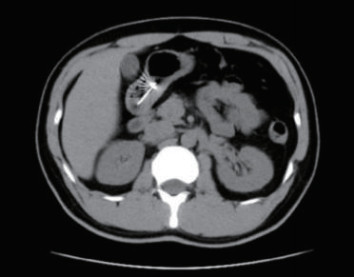

1 一般资料患者,男性,32岁,职员,因“误吞金属钉状物7 d”就诊。患者7 d前误吞入金属钉状物一根(大小约3 cm),患者无明显不适症状,未诊治。4 d前出现下腹隐痛,行急诊全腹CT检查,见图 1,行急诊胃镜检查未见明显异物。后复查腹部CT示异物进入小肠内(图 2),普外科会诊建议随访。2 d前复查腹部CT(图 3),继续保守治疗。1 d前患者为行异物取出入院,复查腹部CT可见异物至结肠内(图 4)。急诊予以聚乙二醇电解质散导泻清肠,行无痛肠镜下异物取出术。本文已通过本院伦理委员会审批,伦理审批号为:(2021)伦审研第(0252)号,并通过免除知情同意申请。完善术前检查,进行药物导泻清肠时,关注患者有无腹痛等现象,以免因服用药物清肠,肠蠕动加快,尖锐异物在消化道内随蠕动前行,尖端嵌插在肠壁中而停滞不前,并随着后方内容物的推进,加深尖锐异物刺入肠壁,最终导致穿孔及出血的发生。本例患者安置在独立单人间进行肠道准备,不定时进行腹部查体及观察排泄物的性状,早期发现穿孔、出血指征,以便尽早进行外科手术干预。与此同时,内镜中心医护人员联合外科、放射科、麻醉科医生制定诊疗方案,若发生此类情况,立即予急诊行腹部X线或CT检查,一旦确定出现穿孔或出血等情况,即刻行急诊手术治疗。

| 图 2 腹部CT示小肠内条索状致密影,周边放射状明显,邻近肠系膜未见渗出和积气 |